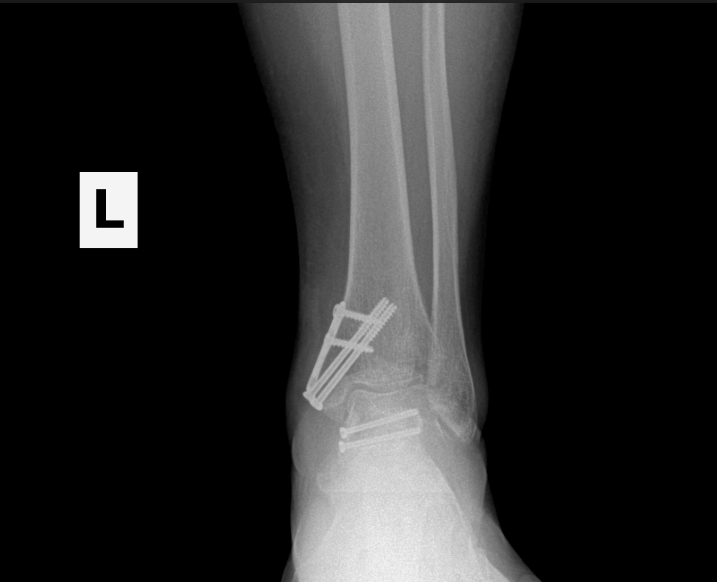

Ankle fracture repair

AF2